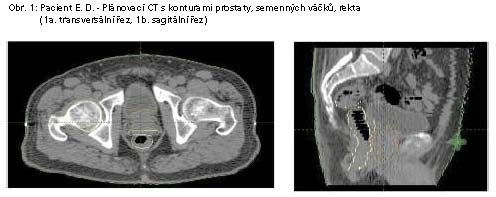

4. Přesnost stanovení cílových objemů. Zpřesnění konturingu

zvyšuje kvalitu aktinoterapie. Objem prostaty, eventuelně prostaty

a semenných váčků, stanovený dle MRI je o 27 - 43% menší proti jeho

stanovení dle CT. Rozdíl v definici apexu prostaty dle MR a dle CT

činí až 1 cm. Ve světě se v současné době již stala standardem pro

plánování RT prostaty MRI malé pánve, která se fúzuje s plánovacím

CT vyšetřením.

- jedná se o obrazem řízenou radioterapii (IGRT). (Obr. 1, 2). Ke